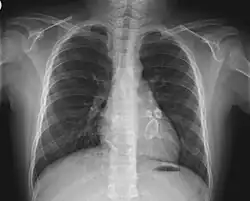

Das Kawasaki-Syndrom oder mukokutane (die Schleimhaut betreffend) Lymphknotensyndrom (englisch mucocutaneous lymph node syndrome (MCLS)) ist eine akute, fieberhafte, systemische Erkrankung, die durch Entzündungen der kleinen und mittleren Arterien (nekrotisierende Vaskulitis) gekennzeichnet ist. Zusätzlich ist eine systemische Entzündung in vielen Organen vorhanden. Die Ursache ist unbekannt; man vermutet eine infektiöse, wahrscheinlich virale Entstehung, die durch eine erbliche Grundlage begünstigt wird. Das Kawasaki-Syndrom betrifft vor allem Kleinkinder. Benannt ist die Erkrankung nach dem japanischen Kinderarzt Tomisaku Kawasaki.[1][2][3][4] Die Prognose der Patienten mit diesem Syndrom ist gut. Für die Erkrankung bedeutsame aneurysmatische Veränderungen, insbesondere der Herzkranzgefäße, lassen sich gegebenenfalls in der Echokardiographie erkennen. Die meist durch Herzinfarkt bedingte Letalität beträgt etwa 1 Prozent.[5]

- Diese treten hauptsächlich in der Frühphase auf und sind maßgeblich für die Langzeitmorbidität und -letalität verantwortlich: Myokarditis (50 %), Perikarditis, Herzklappenprobleme, Aneurysmabildung der Herzkranzgefäße und anderer Arterien, Raynaud-Symptomatik.

Die Diagnose eines kompletten Kawasaki-Syndroms wird klinisch gestellt und erfordert das Fieber und vier von fünf der anderen genannten Kriterien sowie den Ausschluss anderer Erkrankungen mit ähnlichen Symptomen. Dann kann die Diagnose auch schon nach fünf Tagen Fieber gestellt werden. Kinder, die diese Kriterien nicht erfüllen, werden als so genanntes inkomplettes Kawasaki-Syndrom diagnostiziert, wenn unten genannte Nebensymptome und/oder Laborbefunde teilweise oder überwiegend zutreffen. Dies tritt häufiger bei Kindern unter einem Jahr auf und ist hier wegen des erhöhten Risikos von Koronararterienaneurysmen (Nachweis durch transthorakale oder transösophageale Echokardiographie und gegebenenfalls Koronarangiographie[12]) besonders problematisch.

Virale und bakterielle Erkrankungen, Leptospiren, systemische Form der juvenilen idiopathischen Arthritis, Polyarteriitis nodosa, Quecksilbervergiftung. Bei inkomplettem Kawasaki-Syndrom bestehen zahlreiche weitere Verwechslungsmöglichkeiten. Bei Fieber unklarer Ursache sollte besonders beim kleinen Kind frühzeitig an die Differentialdiagnose Kawasaki-Syndrom gedacht werden und neben den Laboruntersuchungen auch eine Echokardiographie durchgeführt werden mit Untersuchung der Herzkranzgefäße.

- Entzündung der Herzkranzgefäße (Koronararterien)

- mit Aneurysmabildung

- oder nach Jahren auftretenden Stenosen

- Myokarditis oder Perikarditis (Herzbeutelentzündung) in der akuten Phase

- Herzinfarkt (häufigste Todesursache: 1 bis 2 %)

- Herzrhythmusstörungen

Herzkranzgefäße

Der Langzeitverlauf der Erkrankung ist davon abhängig, ob Veränderungen an den Koronararterien auftreten. Bei etwa 25 % der unbehandelten Kinder entwickeln sich ein oder mehrere Aneurysmen. In diesem Fall wird die tägliche Einnahme eines leichten Blutgerinnungshemmers, etwa Acetylsalicylsäure (100 mg) bei Kindern empfohlen. Etwa die Hälfte dieser Aneurysmen bildet sich innerhalb eines Jahres wieder zurück. Bei etwa 20 % der Patienten kommt es im Laufe von Jahren zu Stenosen, die unbehandelt wiederum in fast der Hälfte der Fälle zum Herzinfarkt führen.